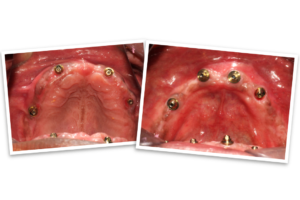

The day of the procedure arrived. Our team strategically placed four implants each in Mr. B’s upper and lower jaw (maxilla and mandible).  The immediate denture was then securely fixed onto the implants, immediately providing him with a functional and aesthetically pleasing smile.